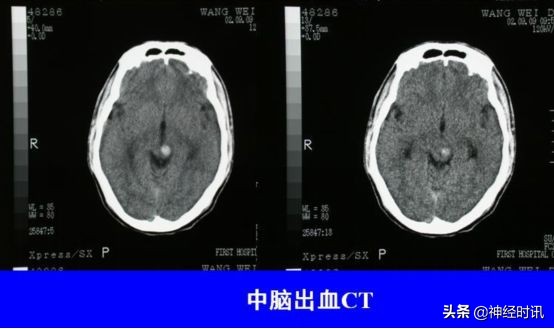

中脑出血

出血量少→同侧或双侧动眼神经损害,眼位异常,伴对侧或双侧锥体束征。

大量出血→深昏迷、双侧瞳孔散大,立即死亡。

头颅CT: 是确诊脑出血的首选检查

① 急性期CT显示高密度影。

② 可显示出血部位,出血量,中线移位,有否破入蛛网膜下腔及脑室,有助于指导治疗和判断预后。